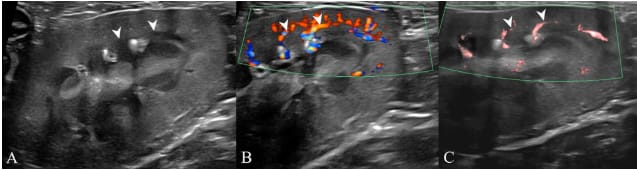

Ultrasound images of the left kidney cortex in the sagittal plane using B-mode, color Doppler imaging (CDI), and superb microvascular imaging (SMI) in a dog with International Renal Interest Society chronic kidney disease stage 1. The white arrowheads indicate the measurement points used for assessing cortical thickness in B-mode (A), CDI (B), and SMI (C). In B-mode, the broad base of the medullary pyramid is identified, whereas in CDI and SMI, the arcuate vessels are used to identify the corticomedullary junction.